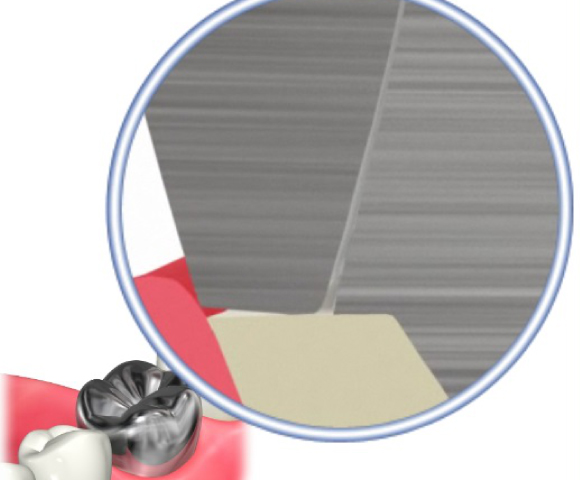

■歯磨きではとれない歯石や合っていない汚れが貯まりやすい被せ物の除去をします。

合っていない冠の除去し仮の歯に

治療前(症例)

治療後(症例)

歯周病治療後被せ物をしっかりフィットさせることで歯周病の再発を防ぎます。

治療前(症例)

治療後(症例)

治療前、被せ物と冠の間に段差がありフィットしていませんが、歯周病治療後しっかりと被せ物をフィットできています。